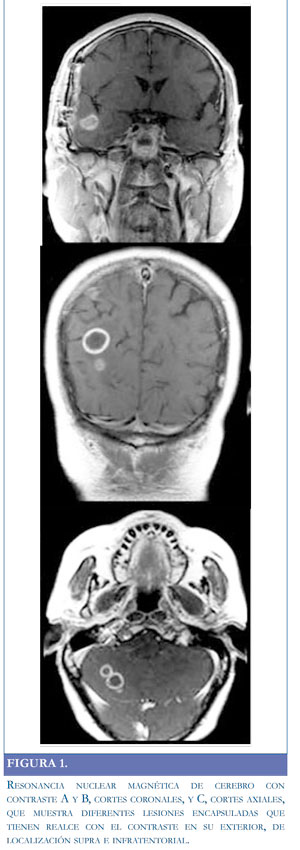

Se hospitalizó para estudio de síndrome parietal derecho y posible ataque cerebrovascular. Laboratorios iniciales, hemograma y química sanguínea, normales. Se tomó resonancia magnética de cerebro simple y contrastada, revelando múltiples lesiones de tamaños variados que comprometían ambos hemisferios cerebrales, la mayoría en el lado derecho, de apariencia redondeada y marcado edema a su alrededor, con realce en patrón anular, y una en hemisferio cerebeloso de similares características que sugieren lesiones metastásicas (Figura 1). En estudios de extensión se encontró en tomografía de tórax una opacidad en el segmento posterior del lóbulo inferior izquierdo con amputación de la luz bronquial para segmentos inferiores del lóbulo inferior. Hasta ese momento el paciente estaba enmanejo anticonvulsivante y analgésico. Se realizó biopsia de pulmón, la cual no fue conclusiva de lesión primaria infecciosa o inflamatoria, considerándose lesión cicatricial a su antecedente de tromboembolismo pulmonar. Los reportes del líquido cefalorraquídeo, incluidos citoquímico, hongos, tuberculosis, criptococo, antígenos bacterianos en la sangre; las pruebas para toxoplasmosis IgM e IgG, y VIH, fueron negativas. En el séptimo día de hospitalización la cefalea se intensificó y se encontraron signos de hipertensión endocraneana dados por diplopía y emesis. Se trasladó a unidad de cuidado intensivo y se inició manejo con esteroides y manitol a dosis adecuadas. Se estabilizó el cuadro y se decidió realizar biopsia cerebral guiada por estereotaxia (lesión parieto-occipital derecha); se aspiró material purulento, pero en el reporte definitivo no se hallan cultivos positivos ni malignidad en la patología. En ese momento el paciente no tenía diagnóstico y por resultado macroscópico de biopsia se inició antibioticoterapia endovenosa de amplio espectro: ceftriaxona, vancomicina, metronidazol, trimetroprim sulfametoxazol (TMP/SMX) y caspofungina.

Las imágenes diagnósticas generalmente reportan lesión multilobulada que realza en anillo con edema perilesional (4, 9). Los estudios con radiotrazadores pueden sugerir absceso (10, 12). Como diagnóstico diferencial se debe pensar en lesiones tumorales primarias o secundarias, vasculitis, ataque cerebrovascular y hematoma en resolución (8, 10, 12-17). Es necesario informar al laboratorio cuando hay sospecha de nocardia, pues los cultivos se pueden demorar hasta cuatro semanas. Es raro encontrar nocardia en la punción lumbar y que el citoquímico del líquido cefalorraquídeo esté alterado (9).